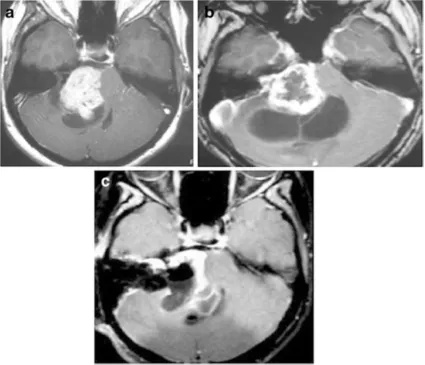

患者,女,58岁,右耳听力下降、耳鸣、头晕3年,初期MRI显示右侧管内型肿瘤略微突入桥小脑角区(图20-1A)。患者接受边缘剂量12.3Gy伽马刀治疗,每年复查一次MRI。放疗2年后发现脑桥小脑角肿瘤轻度增大(图20-1B)。随后患者出现全聋、头晕加重和共济失调。立体定向放疗后三年MRI显示肿瘤增大、压迫脑干(图20-1C)。放疗专家观察3年后接受手术。

图1:A.轴位增强MRI显示右侧内听道内肿瘤,均匀强化(伽玛刀治疗前);B.轴位增强MRI显示肿瘤向脑桥小脑角生长(伽玛刀治疗2年后);C.轴位增强MRI显示肿瘤进一步生长压迫脑干和小脑(伽玛刀治疗3年后),肿瘤中心未强化